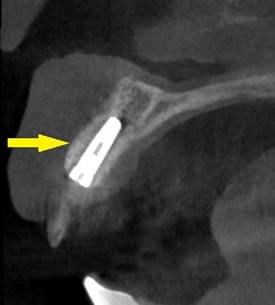

そこで、左側はソケットリフトを併用して行いました。インプラント埋入手術後のCT、黄色の矢印部分、インプラント周囲にドーム状に補填材が白く写り、インプラントがしっかりと埋入できています。